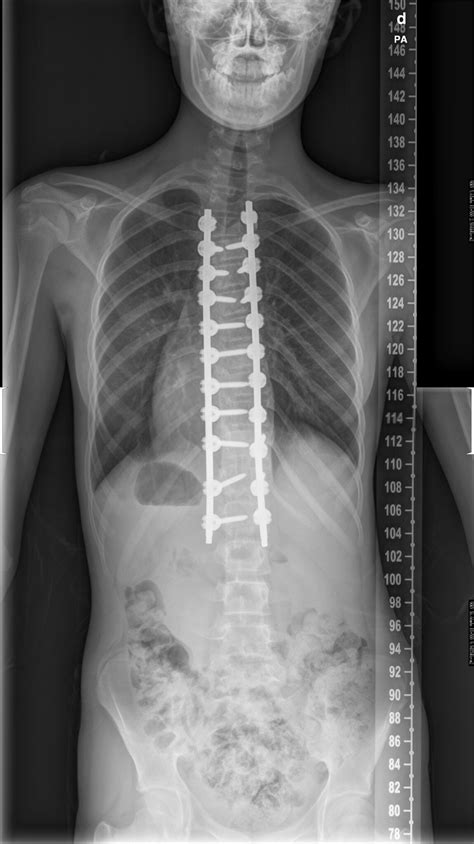

En términos médicos simples, la escoliosis es una desviación lateral de la columna vertebral que hace que esta se curve hacia los lados, formando una figura en "S" o en "C", en lugar de seguir una línea recta vertical. Esta condición puede variar desde una curvatura leve hasta casos graves que requieren intervención médica significativa.

Si notas alguna de estas características en ti o en un familiar, es recomendable programar una cita con un ortopedista para un examen físico completo y una radiografía, que es el estándar de oro para confirmar el diagnóstico.

Reservada generalmente para curvas severas (mayores a 45-50 grados) o aquellas que afectan la función pulmonar o cardíaca. La cirugía (fusión espinal) busca corregir la curva y estabilizar la columna de forma permanente.